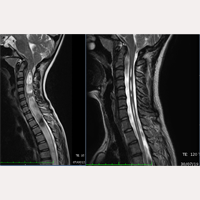

Dall’ottobre del 1993 all’attualità, sono stati in trattamento e operati secondo i protocolli del FILUM-SYSTEM®, più di 2100 pazienti affetti da Sindrome Neuro-Cranio-Vertebrale e/o Malattia del filum con Arnold Chiari I, Siringomielia e Scoliosi, in differenti combinazioni diagnostiche tra le stesse.